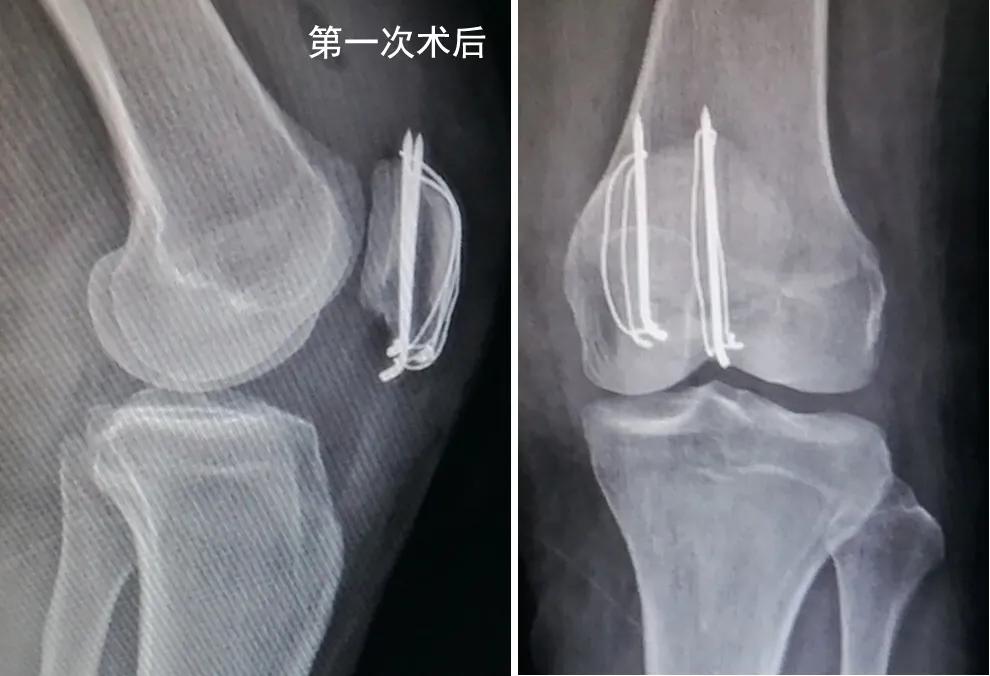

洪女士特意选择当地有名的医院,请骨科主任给她做了切开复位加经典的钢丝克氏针内固定手术。手术很顺利,术后片子显示骨折复位和内固定物位置满意(如下图)。

为了避免膝关节术后粘连,洪女士按照康复师的指导,术后即在关节不疼痛的范围活动膝关节,术后2周拆线后加强膝关节的屈伸练习。为了获得良好的膝关节功能,洪女士咬牙克服康复练习的疼痛,没想到练习2周后膝关节肿痛越来越重。体疗师也感到奇怪,建议洪女士拍个片子看看,果然发现钢丝克氏针松脱了,髌骨下极骨折又分开了(如下图)。

这可怎么办呢?洪女士和家属特别着急,到哪里再次手术呢?通过网络检索,洪女士和家属得知北医三院创伤骨科张志山医生团队采用新型张力带系统治愈了多例类似的髌骨下极骨折。洪女士坐着轮椅来到了张志山医生的门诊。张志山医生仔细检查了洪女士的左膝关节,切口愈合满意,关节活动时疼痛,由于髌骨下极骨折分离,破坏了伸膝装置的连续性,建议再次手术固定髌骨下极骨折。洪女士对第一次手术表达了不满意,认为手术没做好,所以才会造成内固定物松脱。张志山医生给她解释了这个骨折的特殊性,髌骨下极骨折发生于髌骨远端,不累及或者累及较少关节面,其多表现为粉碎性骨折,骨折块相对较小,此外下极是髌腱的起点,应力相对集中,手术固定存在难度。据文献报道,目前有将近10种方法来治疗髌骨下极骨折,说明这个骨折的治疗存在很多问题,各国医生都在想办法解决。洪女士当地医院的医生已经尽最大努力,选择经典的术式来固定她的骨折,术后片子显示骨折复位和内固定物位置都很好,但是由于髌骨下极骨折的特殊性,经典的钢丝克氏针固定技术不能对抗膝关节术后功能练习,所以才出现内固定的失败。张志山医生决定选择新设计的φ3.0mm垫片空心钉组成的新型张力带系统来做翻修手术。术中见钢丝和克氏针已经松脱,部分髌腱撕脱,下极骨折块粉碎。小心复位骨折,拧入带异形垫片的φ3.0mm空心钉(如图)。